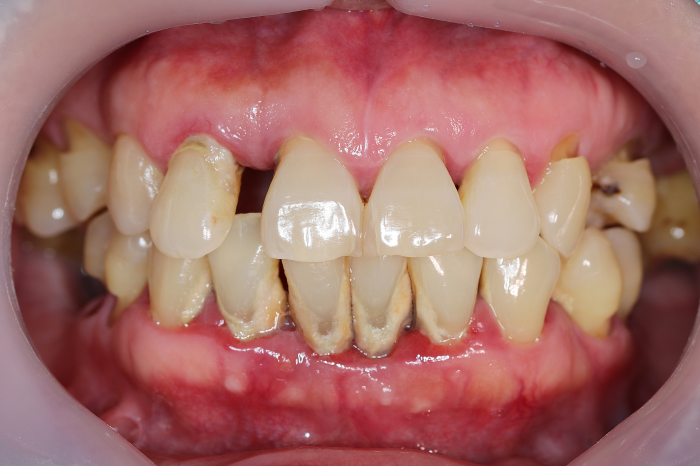

위와 같은 잇몸내려앉음을 예방하기 위해서는

평소 치실이나 치간 칫솔을 통해 꼼꼼하게

양치를 해주어 치아 사이사이 플라크를

최대한 제거해 주는 것이 중요한데요.

또한, 6개월에 한 번씩 정기적인 치과 검진을

통해 잇몸 속에 치석이 쌓이지 않도록

스케일링을 통한 치석 제거 치료를

진행해 주시는 것이 좋습니다.

강남새로치과에서는 잇몸 속에 치은 연하를

쌓이게 만드는 구강 내의 유해 세균과

치아 겉에 붙은 치태, 치석을 체계적이고

효율적으로 제거하는 무통 스케일링을 통해

잇몸내려앉음을 철저히 예방하고 있는데요.

따라서 이를 치료하기 위한 비용과

치료 과정 중 발생하는 통증에 대해

부담감이 컸던 분들이 계시다면

너무 큰 걱정 하지 마시고, 아래 이미지를

통해 메시지를 남겨주시면 효과적으로

치료를 진행할 수 있게 자세한 설명을

도와드리겠습니다 :)